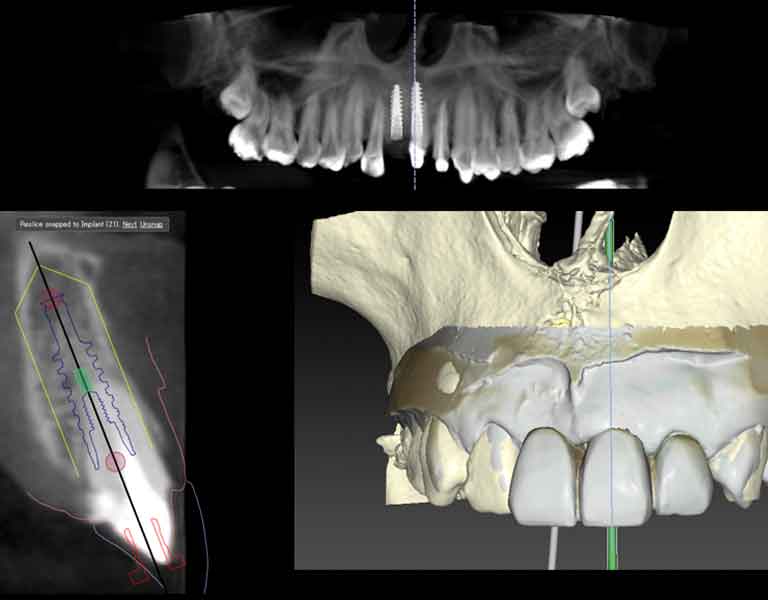

当院では、歯科用CTとレントゲンの複合機である、次世代型歯科用CT スキャン「DEXIS オルソパントモグラフ OP 3D LX」を導入し、高度な診断、お体に負担の少ないレントゲン・CT撮影を行っておりますが、AI搭載診断ソフトウェアDTX Studio™ Clinic ソフトウェアを組み合わせることで、インプラントや矯正治療においてより効率的でメリットを高めた治療が可能です。

DTX Studio™ Clinic は、AIサポートにより、これまで複数のプラットフォームで管理されていた患者さまのさまざまな画像データを一元化してより分かりやすく視覚化、迅速な診断を行うことができる診断ソフトウェアです。

このソフトウェアを使用することにより、インプラント治療や矯正治療における診査・診断をより迅速に、そして治療のイメージを患者さまにもより分かりやすくご覧いただくことができます。

CTのデータと口腔内スキャンで得られたデータを自動的にコンピュータ上で短時間に合致することができ、画面上でリアルなイメージとして見ることができます。

CTデータを読み込むだけで、インプラントを行う場合に解剖学的に重要となる場所の構造や顎関節の詳しい状態の抽出、インプラント手術時に重要になるあごの中の重要な神経の位置の抽出、といったことが自動的に処理されます。

このような作業は従来まではドクターが一つ一つ時間をかけて行っていましたが、AIサポートによりすべての作業を15~20秒程度と劇的に短時間で行えるようになり、診断と治療計画の立案が迅速にできるようになりました。

以上でご紹介したように、AI機能搭載のDTX Studio™ Clinicを使用することで、

・インプラントが可能かどうか

・どんな治療をどのように進めていくことが可能なのか

・かかってくる費用はどのくらいになるか

といった患者さまの知りたい情報を、CT撮影をすればすぐにでも患者さまにもお伝えすることが可能です。また、画面上で治療のシミュレーションを実際にご覧いただくことができますので、具体的なイメージがわきやすく、治療への理解が深まります。

治療計画シミュレーションから埋入までの一連のインプラント治療をより正確にサポートし、予知性・安全性を更に向上させる画期的システム。